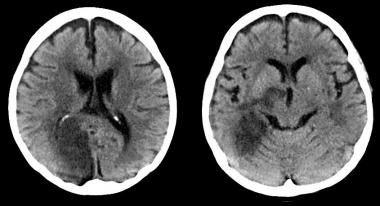

Según un estudio observacional, los pacientes con ictus isquémico y lesiones pequeñas en la tomografía computarizada de perfusión podrían no beneficiarse con la trombolisis. Annals of Neurology, agosto de 2016